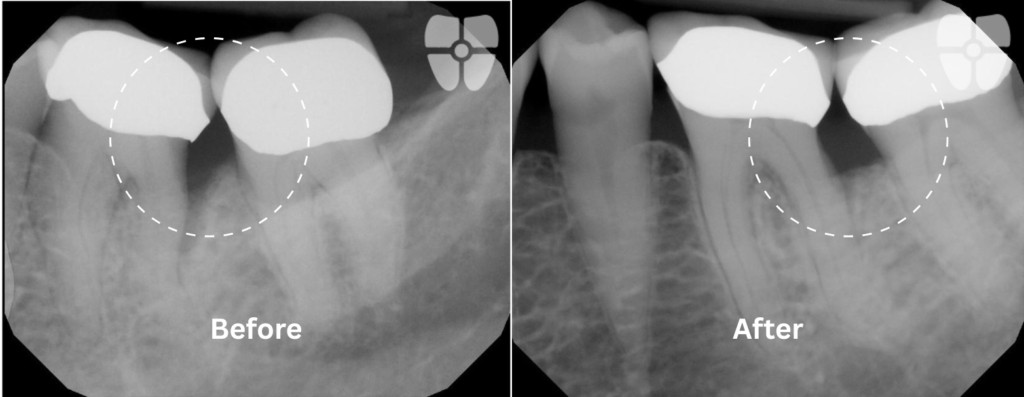

Non-Surgical Flapless Graft using Biological Materials and Periodontal Endoscopic Therapy:

The Results - 9 Months Apart

Real patient results achieved non-surgically with periodontal endoscopic therapy and biologics.

Decrease pocket depth, increase health. Proven to provide 40% less bleeding on probing than traditional periodontal therapies.